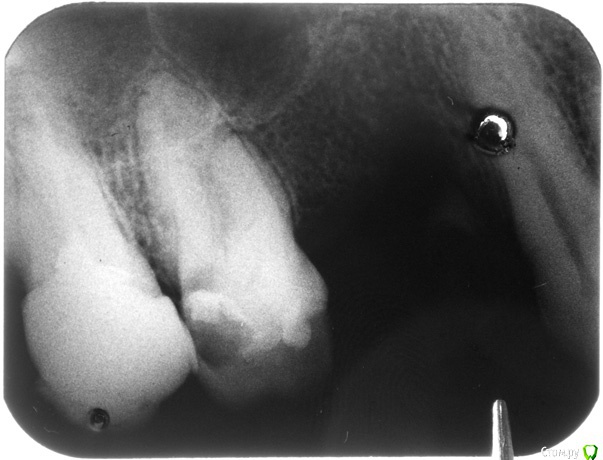

Анбо Опубликовано 15 февраля, 2017 Автор Поделиться Опубликовано 15 февраля, 2017 (изменено) ОПТГ нет. Сходил к другому врачу. Сказала, что снимок плохой (темный), но тоже увидела кариес корня и кисту. Вряд ли они сговорились. Но они зато видели снимок «живьем». Может плохой снимок + потеря качества при перефотографировании привели к тому, что на приведенном здесь фото что-то теряется? Вот поиграл светом-тенью – может что-то проявилось? Это не то, что стрелочками обозначил? Но она была не столь категорична по поводу удаления («Лучше удалить, но можно пока оставить. Но все равно через некоторое время все вернется»). И сказала, что если зуб вскрывать, то будет еще хуже. Мне сделали разрез, чтобы выпустить гной, и назначили азитромицин. Прокомментируйте, пожалуйста.Если на снимке не все видно, укажите, пожалуйста, какие части наиболее важны, я могу в фотошопе сделать их наиболее контрастными. Гистологическое исследование, о котором писал red_butler, не везде делают? Оно имеет какое-нибудь более конкретное название? Изменено 15 февраля, 2017 пользователем Анбо Ссылка на комментарий

Гарриевич Опубликовано 15 февраля, 2017 Поделиться Опубликовано 15 февраля, 2017 это дно верхнечелюстной пазухи"кисты" не видать 5 Ссылка на комментарий

DmitrySH Опубликовано 16 февраля, 2017 Поделиться Опубликовано 16 февраля, 2017 Если у Вас еще сохранились сомнения, то сделайте КТ , все будет понятно. Никакой кисты, просто бухта гайморовой пазухи. 1 Ссылка на комментарий

Bier Опубликовано 16 февраля, 2017 Поделиться Опубликовано 16 февраля, 2017 там четко есть гранулема на медиальном корне. Может ее и назвали "кистой"?? 2 Ссылка на комментарий